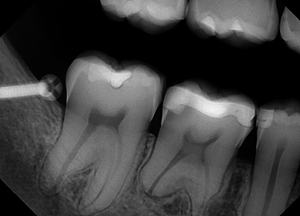

An example of an oversharpened X-ray image

Some doctors want to see their image very sharpened, even what we would call “over-sharpened.” This is OK for several specialties, such as endo, because it allows the apex that they are working on to stand out for more accurate measurements and a clearer canal. When the image is over-sharpened, the image is simply more pixelated than it would ‘normally” be, so if the pixilation doesn’t interfere with anything, then there is nothing wrong with it.